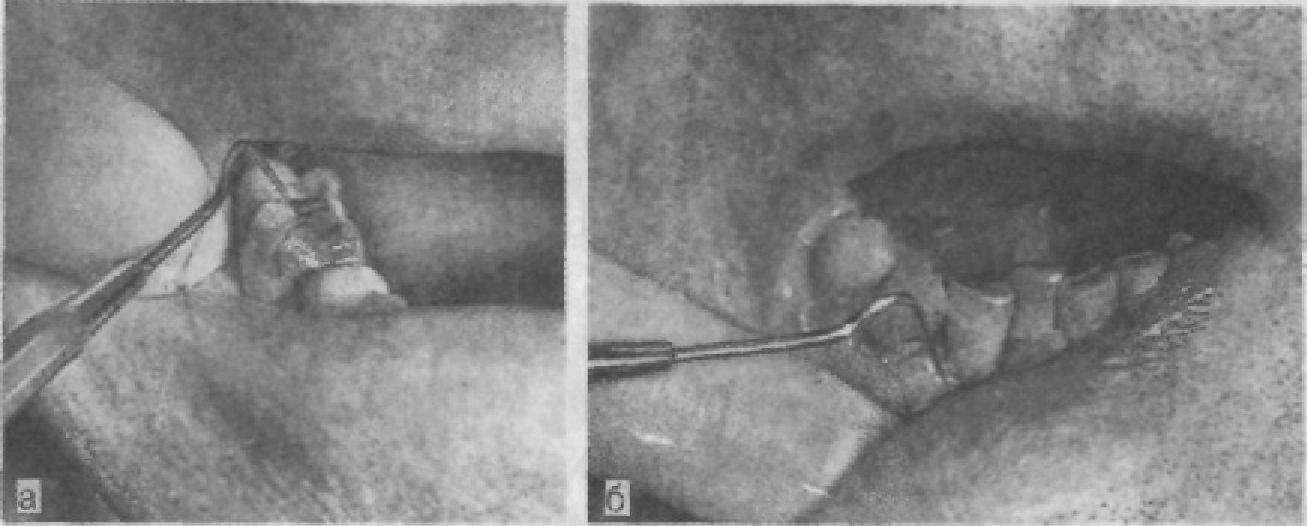

Определяют наличие и глубину периодонтального кармана с помощью углового стоматологического зонда, конец которого обязательно затуплен, а на поверхности нанесены насечки на расстоянии 1 мм друг от друга (рис. 12). Зонд без усилий вводят в десневую бороздку поочередно с четырех сторон: вестибулярной, оральной и контактных. Если зонд погружается надо1ли миллиметра, то говорят об отсутствии пародонтального кармана, иногда его называют зубодесневым, особенно если визуально не установлены воспалительные явления. Критерием определения глубины пародонтального кармана является сопоставление величины погружения зонда с вертикальным размером коронки, который приблизительно в 2 раза меньше длины корня (а следовательно, и вертикального размера стенок альвеол). При воспалении и значительном отеке тканей маргинального пародонта и при гипертрофическом гингивите создается ложное впечатление об образовании патологического десневого кармана. Погружение же зонда от анатомической шейки зуба на половину вертикального размера коронки свидетельствует о глубине поражения, равной 7

Рис. 12 Положение зонда при обследовании коронки зуба (а) и десневой бороздки (б).